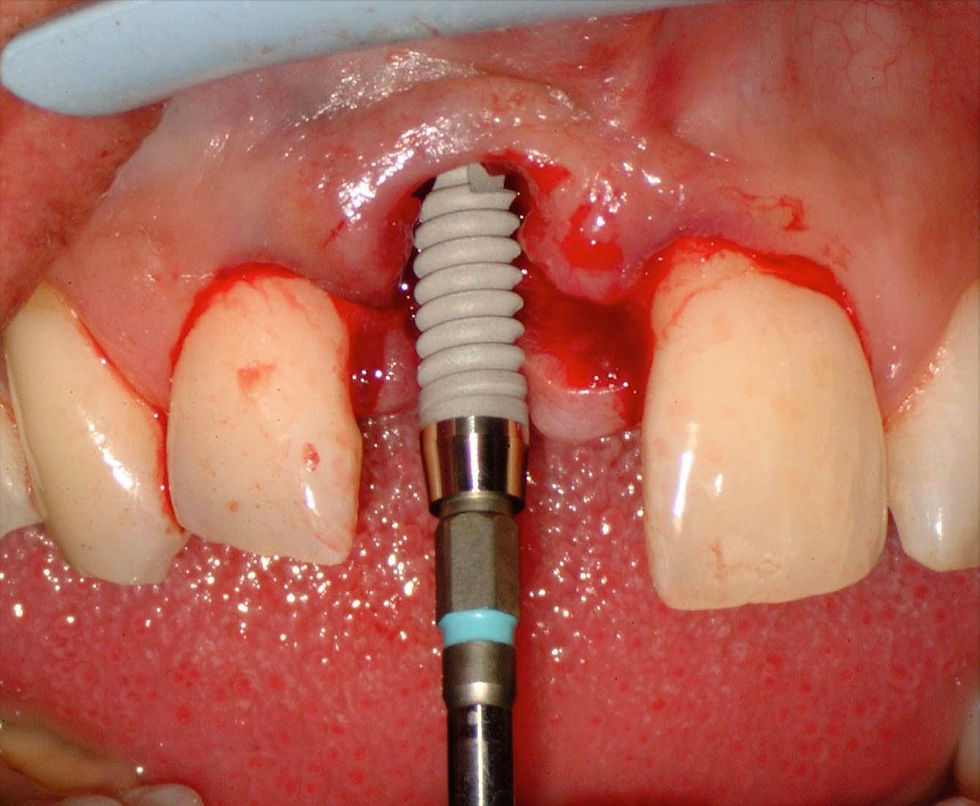

Surgical phases of the insertion of a 11.50 mm high Prama implant.

Note how the positioning of the implant platform is at the level of the cement-enamel junction of the adjacent teeth, an important reference to obtain an ideal condition for the following prosthetic phases.